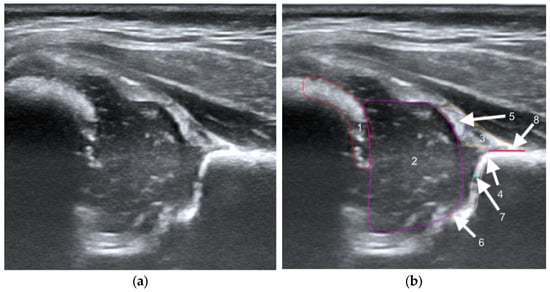

Figure 1. Ultrasound image of the hip in Graf standard plane (a) and labeling of anatomical structures (b). The labeled diagram (b) includes 5 anatomical structures, i.e., chondro-osseous border (red-1), femoral head (purple-2), cartilaginous roof (yellow-3), bony roof (beige-4), and labrum (light purple-5). Other landmarks include lower limb (orange-6), bony rim (light blue-7), and baseline (pink-8).

The structures were annotated by three independent orthopedic surgeons trained in the Graf method who had participated in a Graf-accredited course. The contours of the anatomical structures in the US images were marked using points along the edges of the target anatomy by dedicated software on selected frames. In the annotation process, a maximum of 25 frames from each video were selected by the reporting physician as the best. Annotating physicians selected structures for marking from a drop-down list among the objects on Checklists I and II according to Prof. Graf, necessary for the assessment of hip joints for DDH (Figure 1). Frames were selected for annotation only when it was possible to mark 5 or more objects. Furthermore, at least one selected frame in each video was classified as diagnostic, according to the Graf methodology (standard plane) [14].